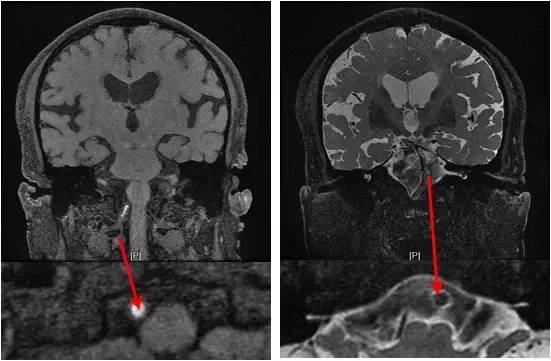

HR-MRI:右椎动脉V4狭窄段管腔斑块强化,基底动脉管壁增厚,可见管腔流空(图7)。

图7

●1.手术指征:患者有反复后循环缺血发作,内科药物治疗下右椎动脉V4重度狭窄进行性加重甚至存在闭塞可能,左侧椎动脉V4闭塞,椎基底系统考虑为责任血管,基底动脉造影未见顺行显影,结合高分辨核磁信息,考虑管腔通畅,但不除外存在狭窄。拟处理右椎动脉V4段狭窄。